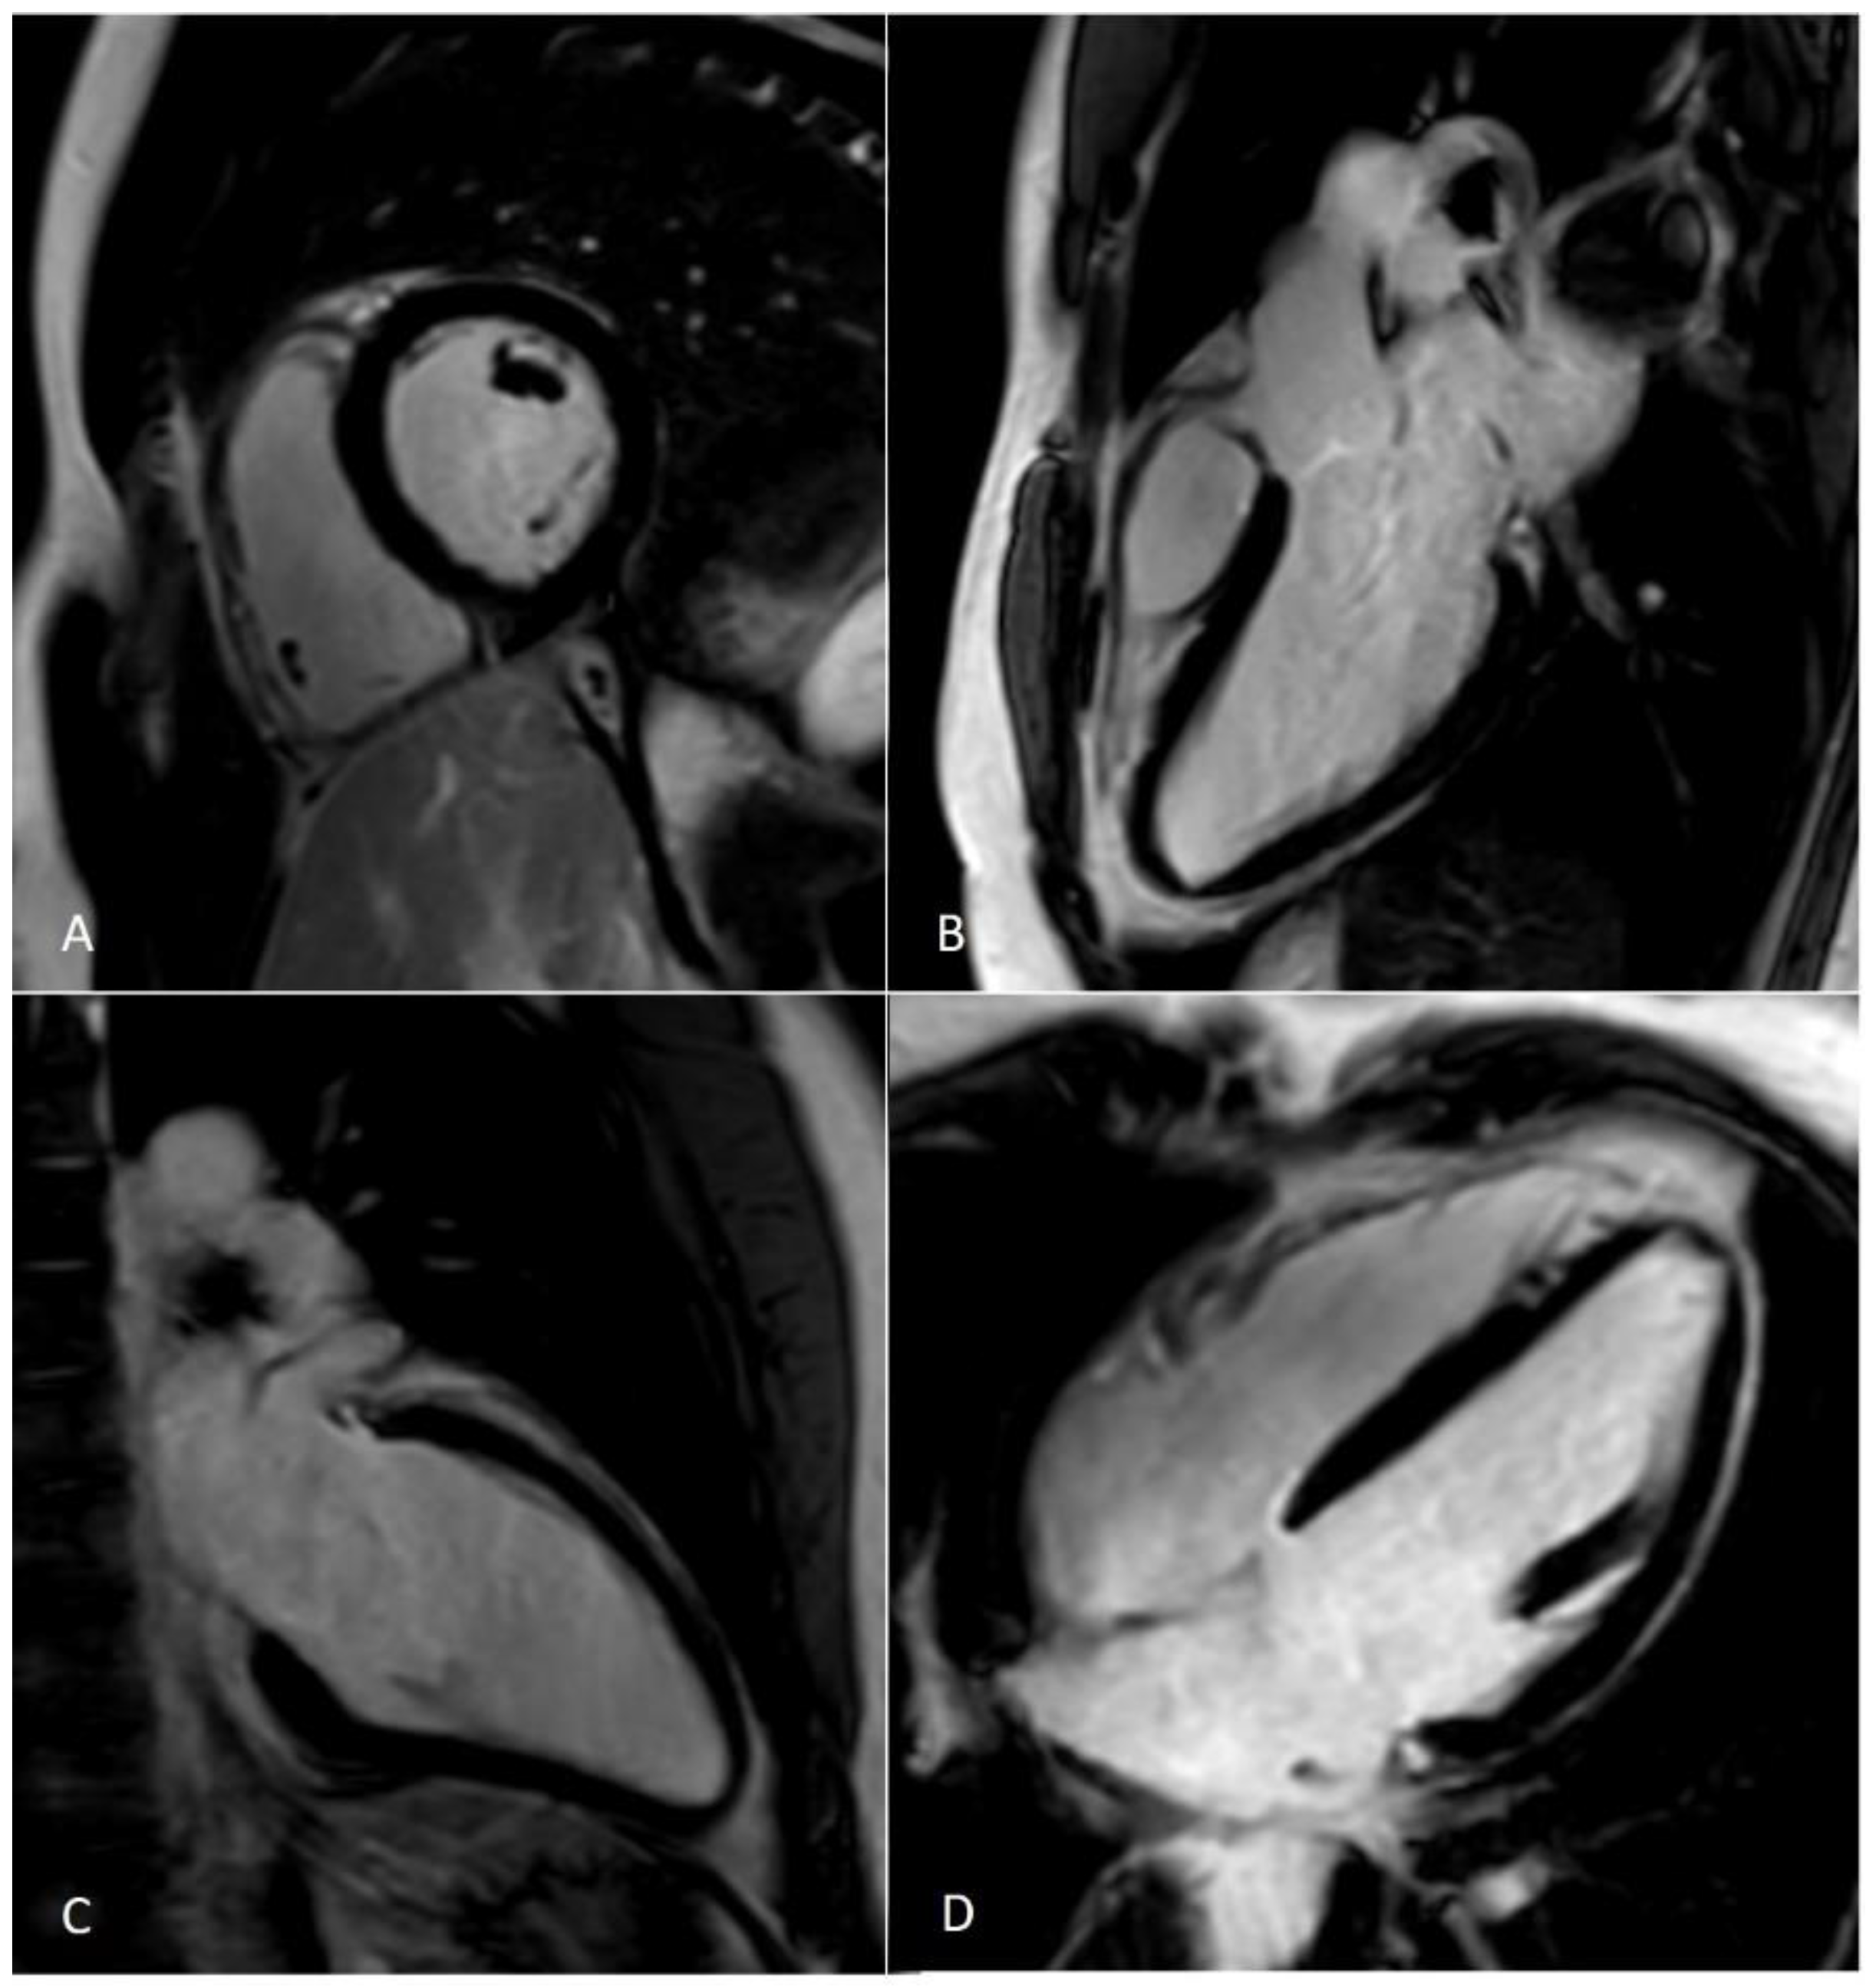

Figure 4.

LGE —late gadolinium enhancement sequences acquired using the compressed sensing technique. Panel (A)—Left ventricle (LV) and right ventricle (RV) short axis view at the level pf the papillary muscles; (B)—LV three chamber view; (C)—LV two chamber view; (D)—LV and RV four chamber view.